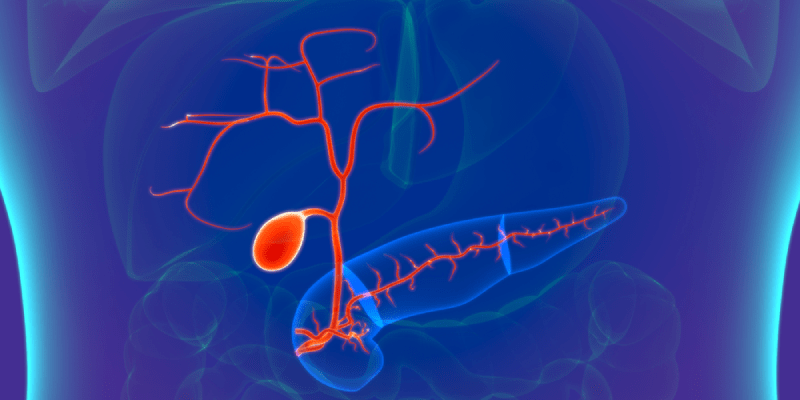

1. Introduction to Klatskin Tumor 1.1 Definition and Characteristics Klatskin tumor is a specific type of cholangiocarcinoma that develops at…

1. Understanding Bile Duct Cancer Bile duct cancer (cholangiocarcinoma) can develop in both intrahepatic (within the liver) and extrahepatic (outside…

1. Introduction to Bile Duct Cancer Bile duct cancer is classified based on its location: This cancer may grow slowly…

1. Introduction to Bile Duct Cancer (Cholangiocarcinoma) Bile duct cancer refers to a group of cancers that originate in the…

1. Understanding Gallbladder Cancer 1.1 Overview and Epidemiology Gallbladder cancer is the fifth most common gastrointestinal cancer, but its incidence…